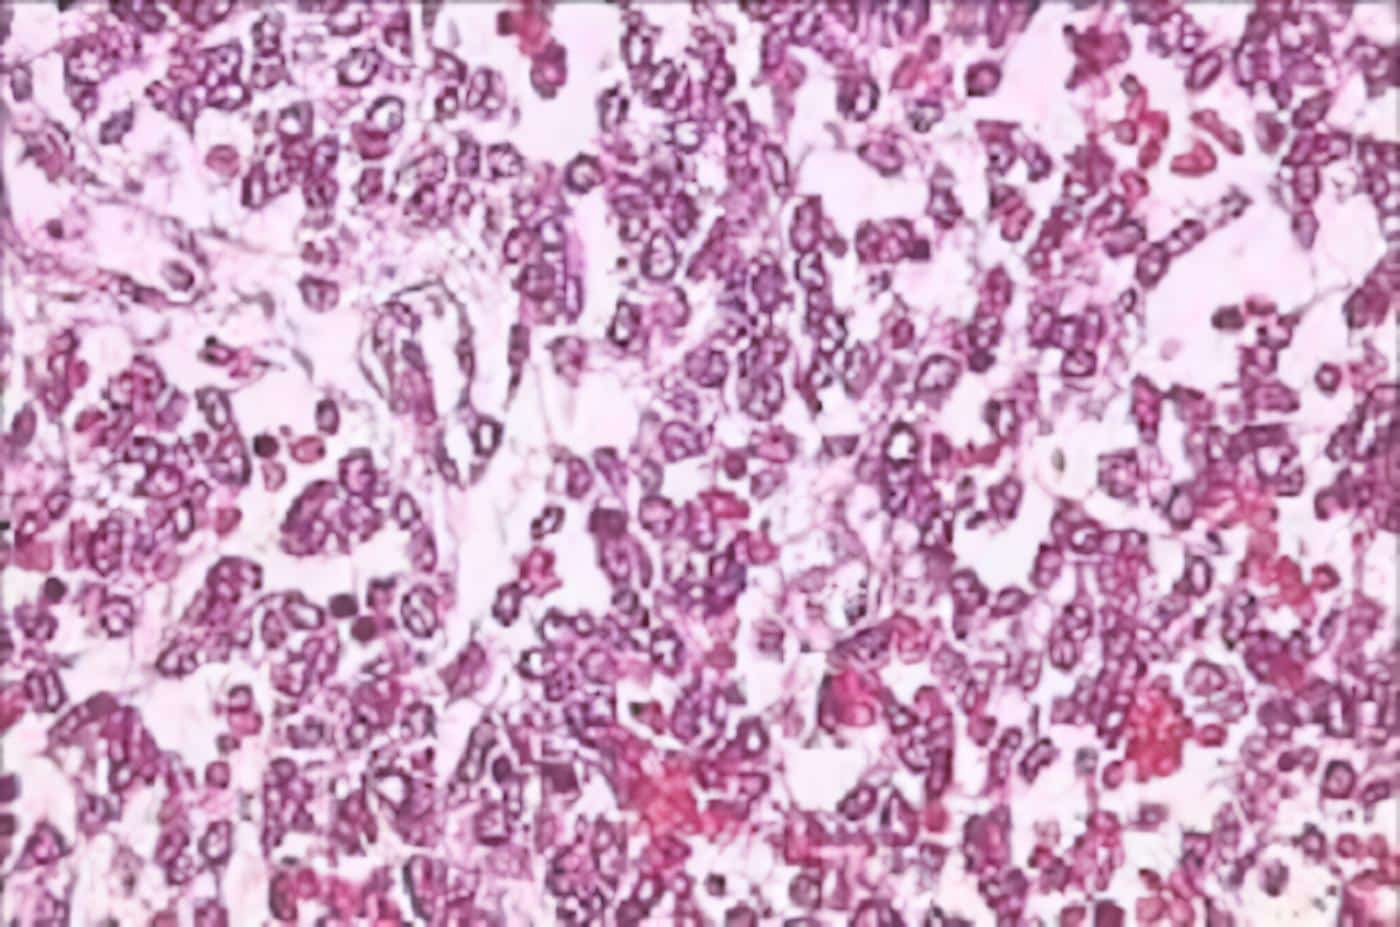

Se demostró al examen microscópico que corresponde a neoplasia no encapsulada, de bordes irregulares, compuestas por lóbulos de tejidos cartilaginosos mezclados íntimamente con elementos epiteliales (Figura 2). El componente cartilagíneo es de celularidad levemente aumentada, sin presentar atipías ni mitosis (Figura 3). El componente epitelial se dispone formando estructuras tubulares papilares irregulares y en brotes sólidos. Corresponde a células de tamaño grande, con poco citoplasma, núcleo aumentado de tamaño, con cromatina gruesa, en partes vesiculosas, con uno o más nucléolos y numerosas figuras mitóticas [hasta 10 en 10 campos de aumento seco mayor] (Figura 4). Hay áreas con necrosis central de tipo comedocarcinoma (Figuras 5 y 6). El tumor contacta la epidermis hacia sus extremos (Figura 7), formando una especie de invaginación periférica y presenta abundantes células plasmáticas como elementos inflamatorios asociados (Figura 8). Focalmente hay túbulos con células de núcleos más pequeños, sin atipías, mitosis y presentando diferenciación apocrina con decapitación de la zona apical de sus citoplasmas.

Figura 4. Células con núcleos grandes, de cromatina gruesa y numerosas mitosis.